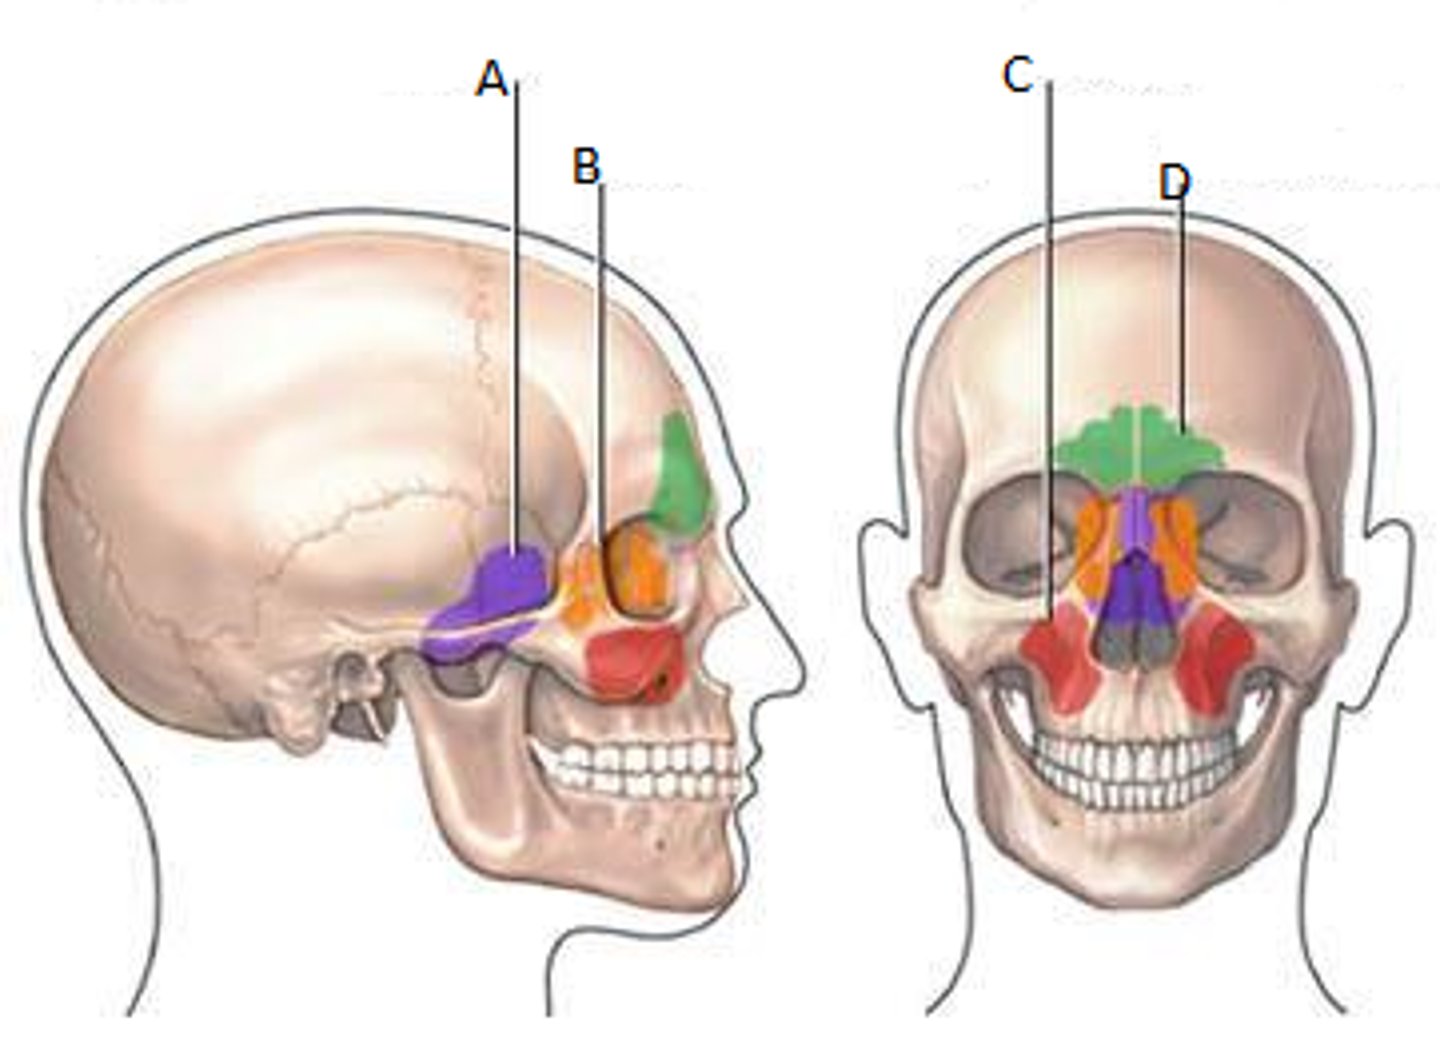

Frontal sinuses

Green

Sphenoid sinuses

Orange

Ethmoid sinuses

Purple

Maxillary sinuses

Red